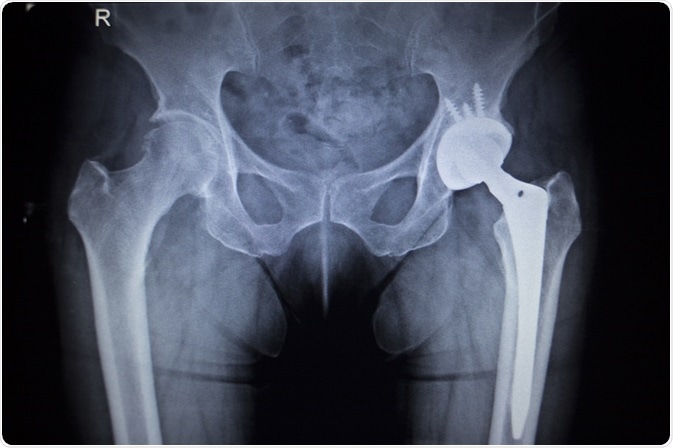

Image credit: Shutterstock | edwardolive

The human body has the ability to heal itself, but in the case of complex or multiple fractures or life-threatening disease or infection, the lack of the original bone hinders the healing process. In these scenarios, a bone scaffold or graft is needed to support bone regeneration and fusion. Also, it may be necessary to use implanted devices, such as joint replacements, plates or screws to replace or reinforce damaged or weak bones and joints. Similarly, implants may be needed in dentistry to help artificial replacement of a tooth root. These implants are typically in the form of a metallic screw placed in the jaw bone to provide support to one or more false teeth.

Implants are widely used in orthopaedic surgery to facilitate the repair of damaged or missing bone as well as in dental reconstructions. Although implants have been employed with a high success rate, rejection issues and toxicity concerns may put limitations on the procedures available. Also, it may require several months for integration of an implant into the recipient bone and therefore, the risk of failure and recovery times will be high.